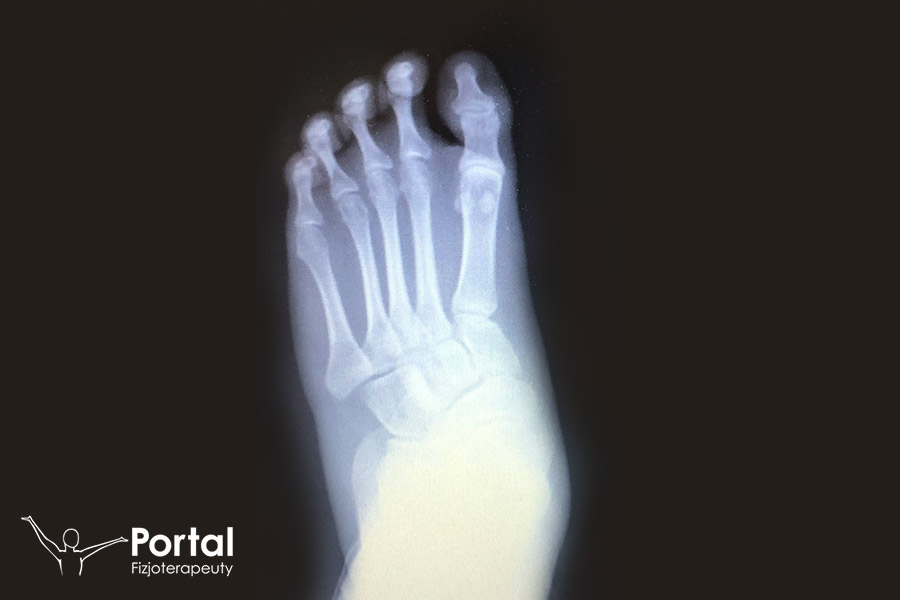

Operacja płaskostopia

Operacja płaskostopia może obejmować kilka różnych technik korekcji tej wady postawy, a dobiera się je indywidualnie do potrzeb danego pacjenta. […]

Osteotomia SCARF

Osteotomia SCARF to jedna z chirurgicznych metod leczenia palucha koślawego, czyli tzw. haluksa. Wymaga wykonania podłużnego nacięcia skóry wzdłuż przyśrodkowej